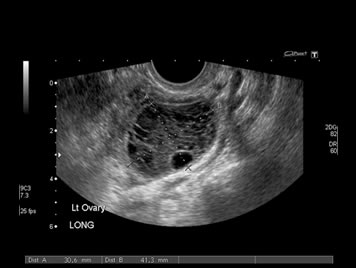

Our professionals at EWH are trained to use state of the art ultrasound technology to provide ultrasound diagnoses